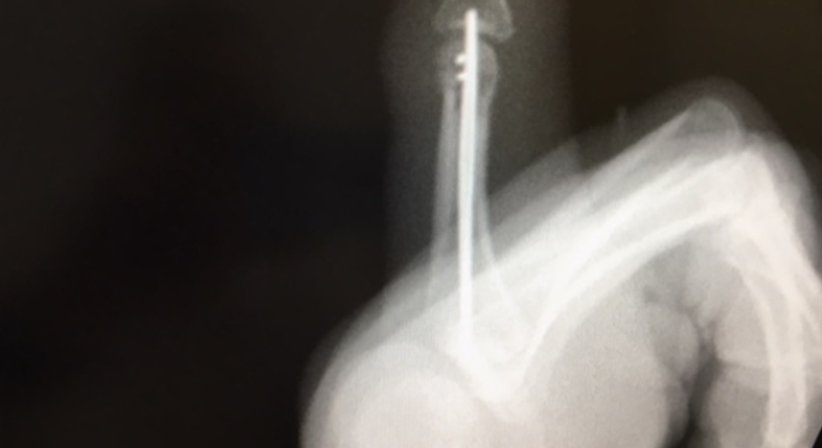

Versorgung von Knochenbrüchen

Osteosynthesen - OA Dr. Andreas Mondl - Unfallchirurg Wien 1220